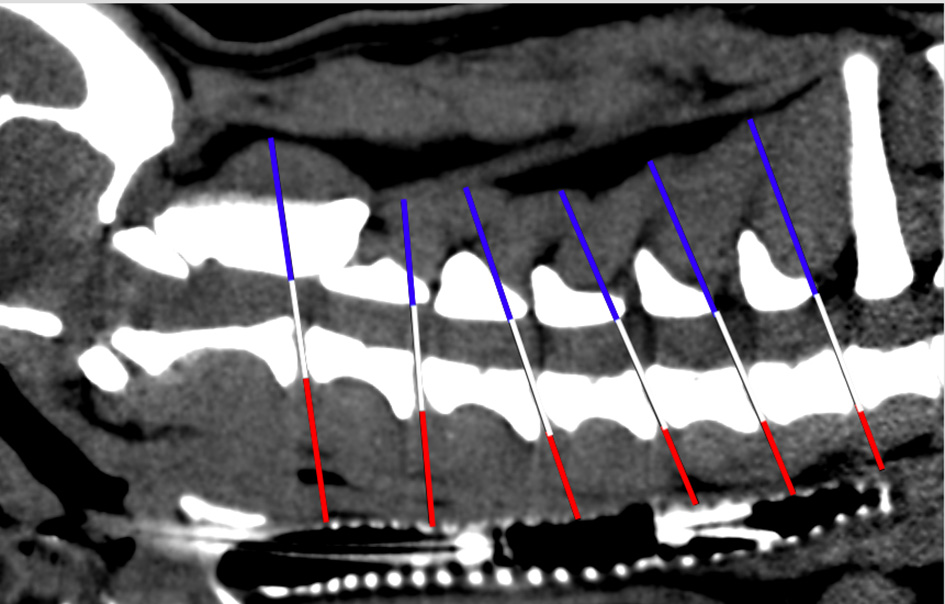

Angle Measurement

Angles between the IVD spaces regarding the axis of the cervical vertebral column were measured (1). Angle measurement aimed to evaluate disk angulation and its potential influence on the load on each cervical IVD. Consequently, a line was drawn on the floor of the vertebral canal connecting the cranial and caudal endplates of the cervical vertebral bodies. After that, a second line was drawn from every caudal endplate in the same axis as the IVD space to the dorsal margin of the trachea. The angle was finally determined between those two lines at each cervical IVD space (Figure 3). For both FB groups, a mean angle was calculated and compared.

Figure 3

Scheme of angle measurement in sagittal plane CT image. White line: level of each cervical intervertebral disk space; blue lines: angles between IVD spaces in relation to the axis of the cervical vertebral column.